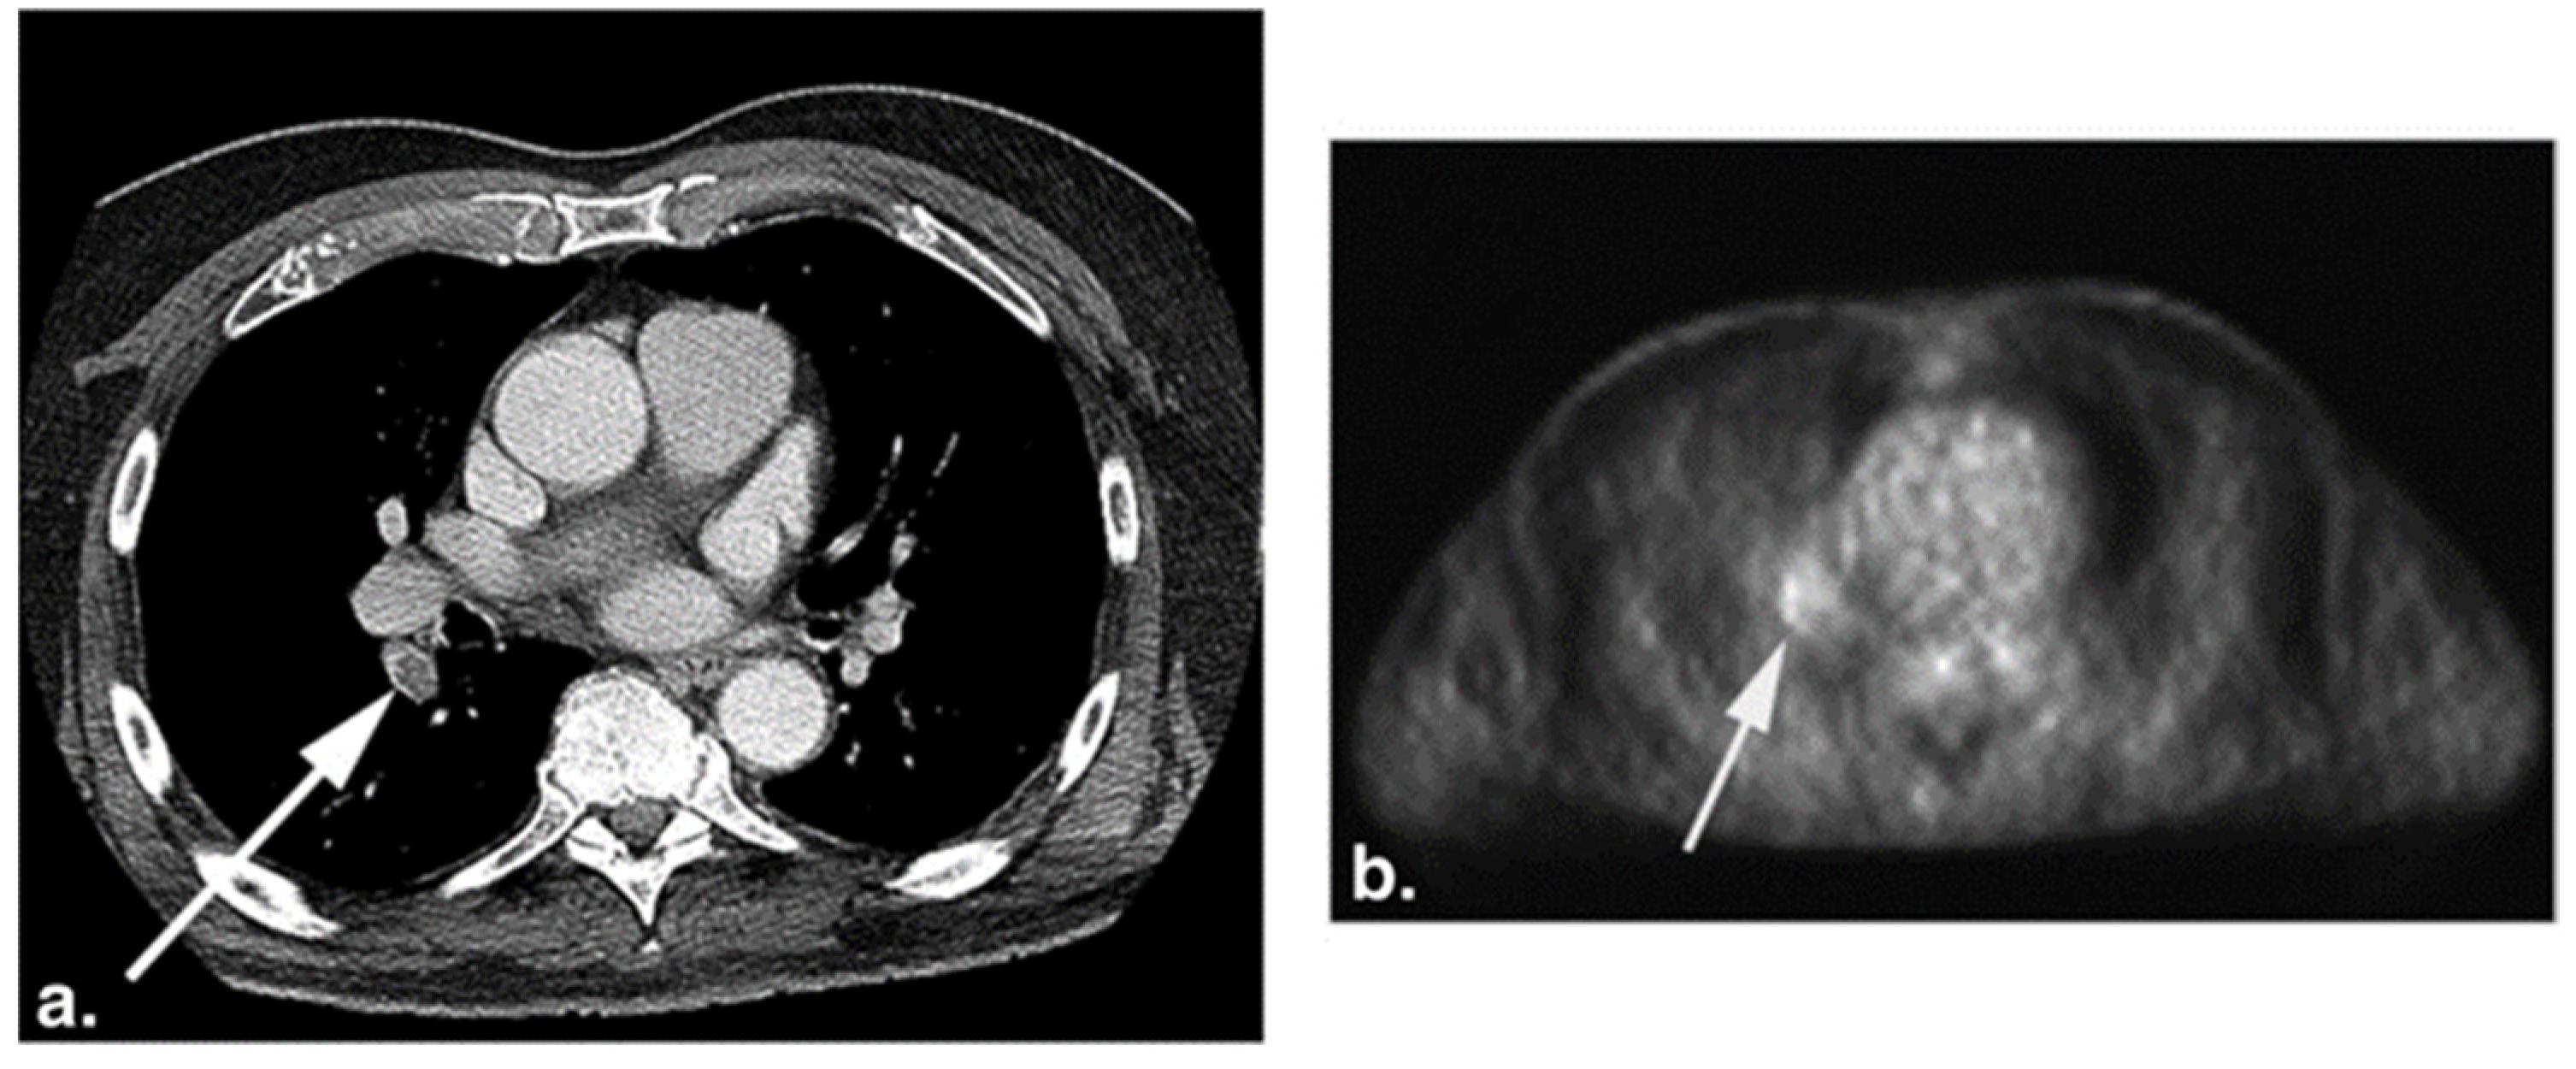

Figure 4.

CT (a) and the corresponding FDG-PET (b) images of a 75-year-old woman with a history of melanoma. The white arrows point to pulmonary embolism (PE) present in the right lower lobe segmental artery. Increased FDG uptake (b) is seen at the location of PE on the PET image (from Flavell et al. [119] with permission).